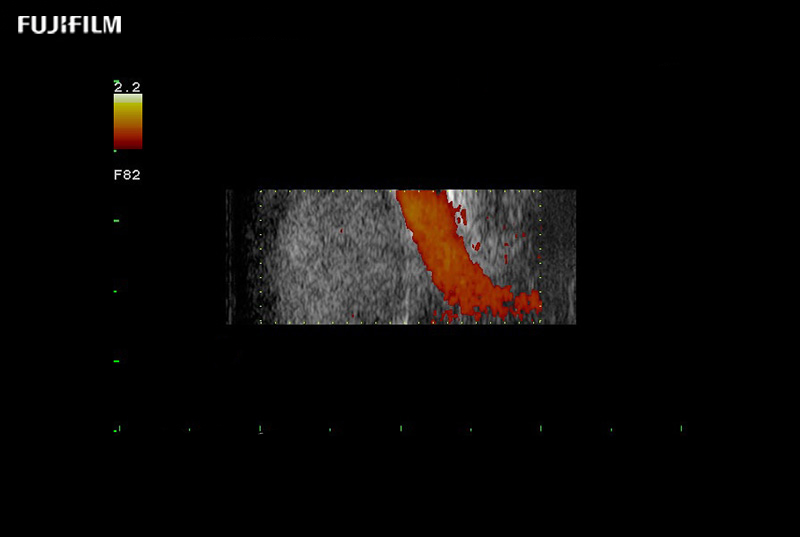

Exclusive 10mm side‐fire linear array transducer with 2.87mm diameter is ideal for real‐time visualization through and behind structures and instant, scalable definition of anatomy and vascularity including the ability to delineate and define tumor margins.

Main Specifications: